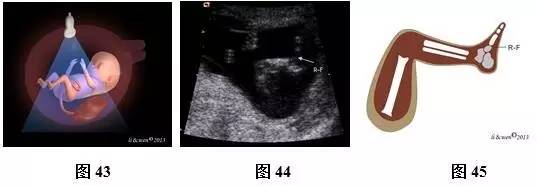

(四)11~13+6孕周胎儿肢体扫查方法及观察内容

超声扫查方法:声束平面通过一侧上肢作冠状或矢状扫查(图40),即可获得一侧上肢冠状或矢状切面(图41,42);声束平面通过一侧下肢作冠状或矢状扫查(图43),即可获得一侧下肢冠状或矢状切面(图44,45)。对每一肢体按此方法逐一扫查,不漏检任何一条肢体。

标准切面判断标准:上肢冠状或矢状切面:应显示上臂及其内的肱骨,前臂及其内尺、桡骨,手掌及手指。下肢冠状或矢状切面:应显示大腿及其内的股骨,小腿及其内胫、腓骨,足。

主要观察内容:骨的长度、回声强度、数目及形态,肢体是否存在或缺如,手及足形态是否正常。此孕期胎儿呈张手状态,易观察到手指数目。

注:R-H为右手;R-F为右足

图40~45 11~13+6孕周胎儿肢体扫查方法及声像图及模式图。图40上肢扫查方法模式图;图41、42右上肢冠状切面声像图及模式图;图43下肢扫查方法模式图;图44、45下肢矢状切声像图及模式图